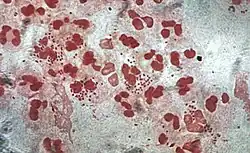

Monocytes develop in the bone marrow and reach maturity in the blood. Mature monocytes have large, smooth, lobed nuclei and abundant cytoplasm that contains granules. Monocytes ingest foreign or dangerous substances and present antigens to other cells of the immune system. Monocytes form two groups: a circulating group and a marginal group that remain in other tissues (approximately 70% are in the marginal group). Most monocytes leave the blood stream after 20–40 hours to travel to tissues and organs and in doing so transform into macrophages[69] or dendritic cells depending on the signals they receive.[70] There are about 500 million monocytes in one litre of human blood.[3]

Neutrophils are normally found in the bloodstream and are the most abundant type of phagocyte, constituting 50% to 60% of the total circulating white blood cells.[77] One litre of human blood contains about five billion neutrophils,[3] which are about 10 micrometers in diameter[78] and live for only about five days.[39] Once they have received the appropriate signals, it takes them about thirty minutes to leave the blood and reach the site of an infection.[68] They are ferocious eaters and rapidly engulf invaders coated with antibodies and complement, and damaged cells or cellular debris. Neutrophils do not return to the blood; they turn into pus cells and die.[68] Mature neutrophils are smaller than monocytes and have a segmented nucleus with several sections; each section is connected by chromatin filaments—neutrophils can have 2–5 segments. Neutrophils do not normally exit the bone marrow until maturity but during an infection neutrophil precursors called metamyelocytes, myelocytes and promyelocytes are released.[79]